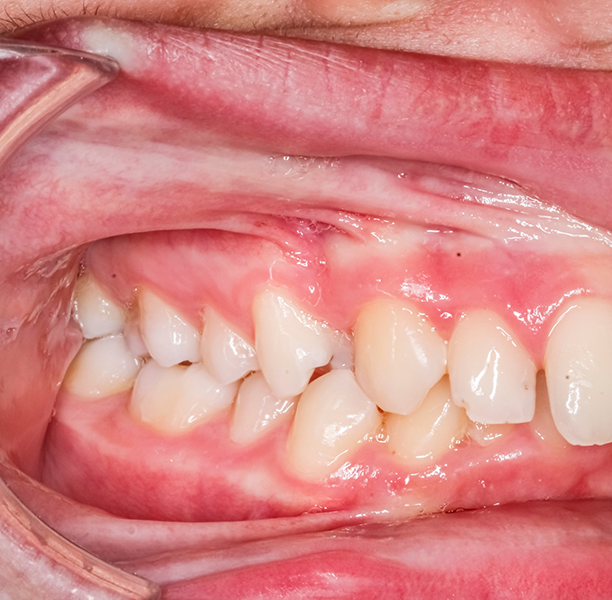

Dentistry is an exciting, ever-changing field. Experts have varying opinions on a wide range of topics, particularly occlusion. Occlusion refers to the way the teeth contact one another, both when the mouth is at rest (static occlusion) and when a person is chewing (dynamic occlusion).

You may have noticed that the education you received in dental school was fairly basic, especially when it came to occlusion. We, on the other hand, place a large emphasis on occlusion because it plays such a big role in a restoration’s long-term viability. For example, not only do we ensure that restorations have even contact, but we also make sure that the positions of the opposing teeth are unlikely to shorten a restoration’s lifespan by placing extra stress on it.

For example, if Dr. Lamberti is designing a crown for a dental implant, he does more than make sure the crown fits in well with the teeth that are adjacent to it. He also considers the position of the opposing tooth (or teeth). If the opposing tooth has shifted out of its anatomically correct position, an interference results, and bite forces are incorrect. This affects both the crown’s long-term viability and the patient’s biting function capability.